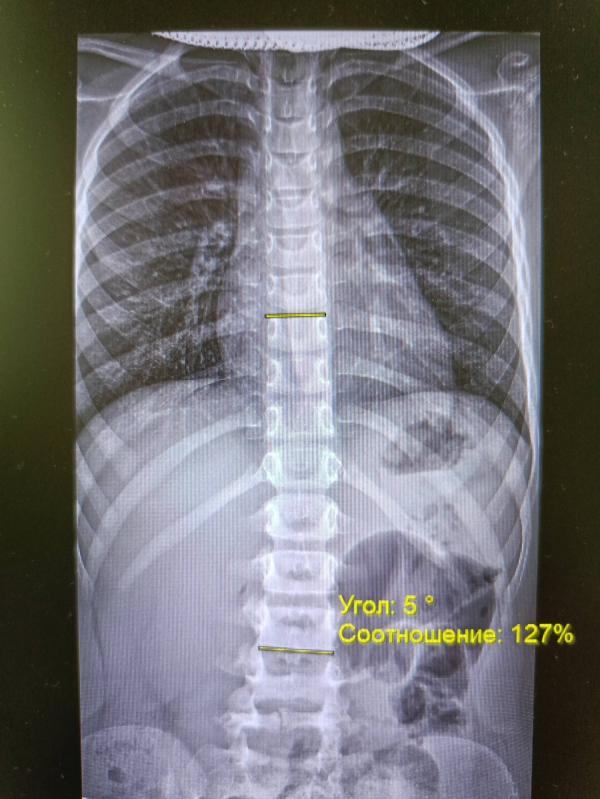

Значит дано, контроль осанки 3год у старшей дочки. 17п-ка в этом году смотрит снимок ставит диагноз сколиоз 1ст с углом 10.5гр ставит нас на учет.

Рустамов в лодэ. Смотрит снимок , сколиоза 1ст нет ⛔ ставит угол 5гр